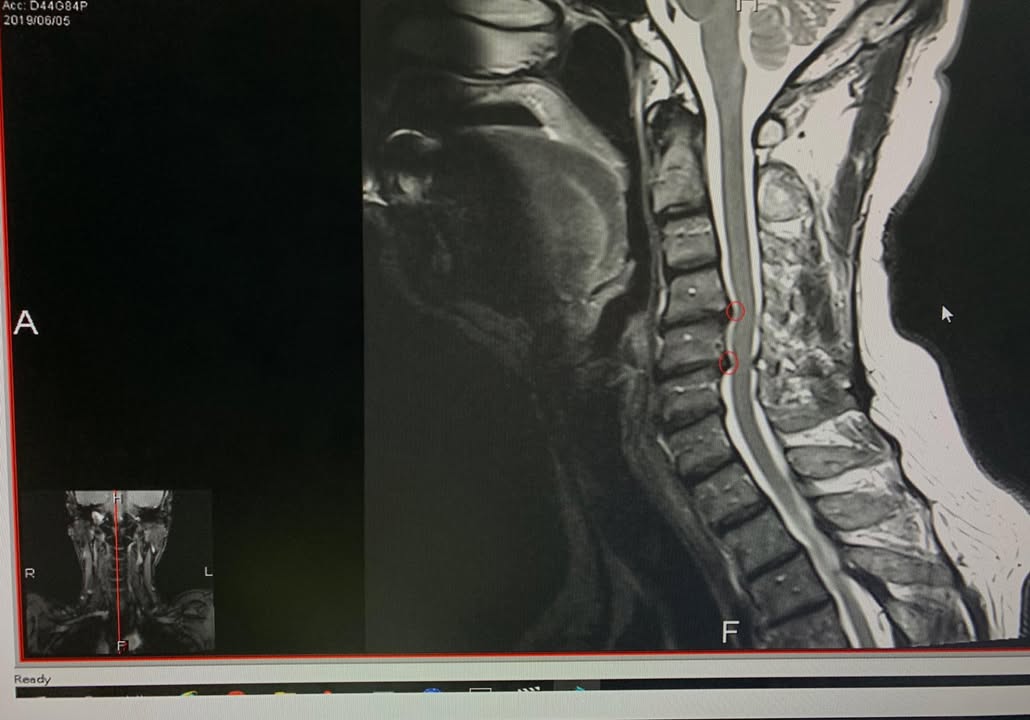

😂😂年過花甲的林大哥抱怨左邊頸痛連肩膀,最近這三個月明顯惡化,頭往後馬上有麻電感,之前長期需要低頭打字密集使用頸部肌肉群,一開始只是肩膀痠痛,後來最近發現整條手臂就開始麻痛才覺得不對勁,去台北榮總醫學中心接受頸椎mri核磁共振照影顯示頸椎第四第五輕微突出導致神經根卡壓(如圖),醫師建議如果復健效果不好則可能要接受頸椎人工關節墊片置換術,經過友人介紹接受頸椎整合中醫微創療法,非常幸運六次效果就很明顯,這幾次去爬山跟日常生活動作發現手的麻痛感大幅度降低,非常開心,這次治療好徐醫師提醒頸部跟肩膀肌肉要適時放鬆跟強化頸部深層肌肉的力量才不會再度復發